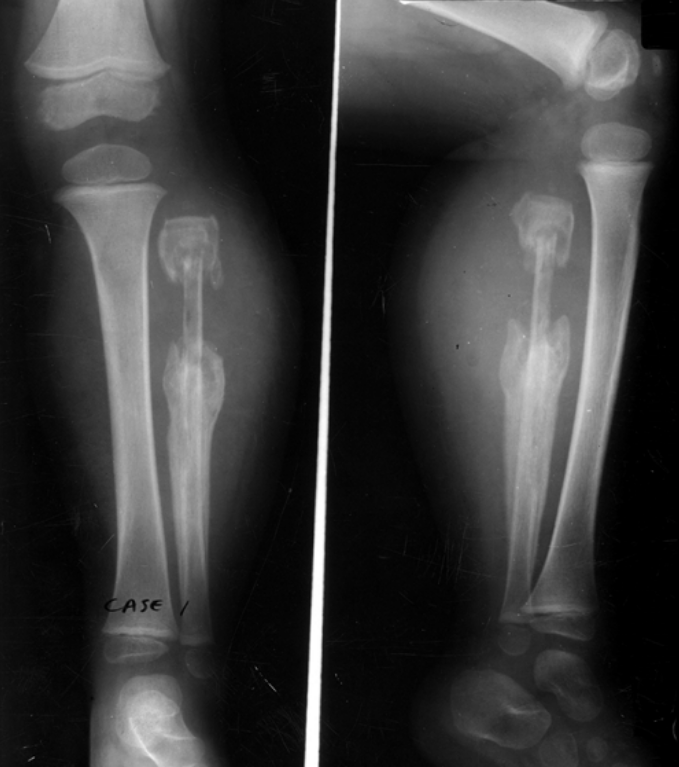

3-year-old male presents with leg pain and swelling. He is radiographed several days into his symptoms.

What radiographic infectious terms are present?

A

• Sequestrum

• Involucrum

• Cloaca

osteomyelitis

permeative lytic destruction (aggressive)